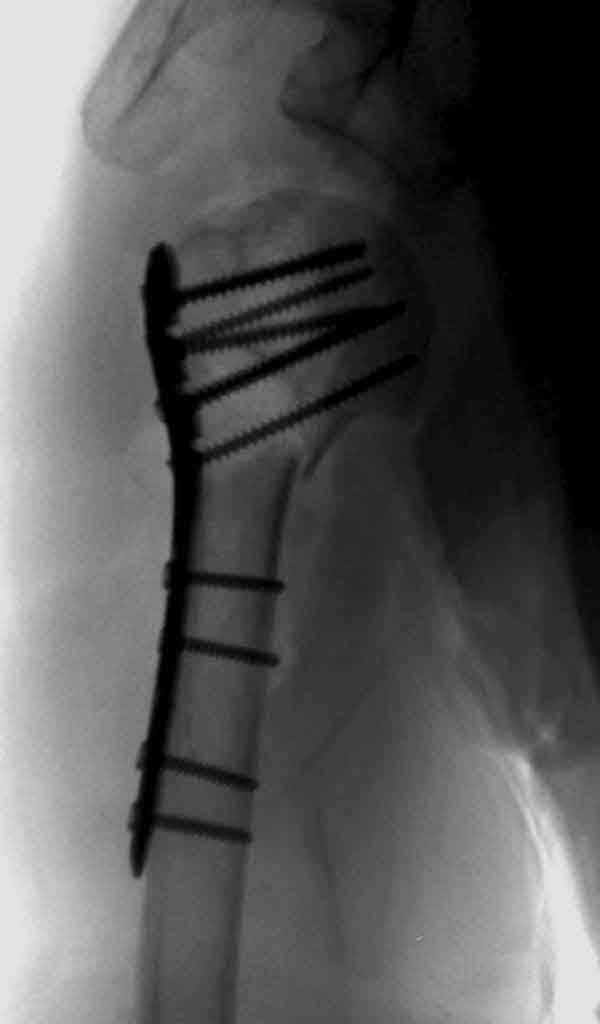

Набор мелких снимков не отражает истинную картину суставной поверхности лопатки, а также качество репозиции головки плеча. Необходимо доказать аксиальным снимком наличие покрытия головки. Правильная маркировка на рентген снимках и соответствие с выставленным диагнозом гарантирует от ошибок со стороной во время операции!

Здесь результат похожего случая, больная 87 лет, отягощенная сердечными делами и два года назад установка pacemaker и нескольких стентов. На третий день, сегодня утром сделали операцию. Послеоперационный псевдовывих связанный с релаксацией мышц и общим обезболиванием.